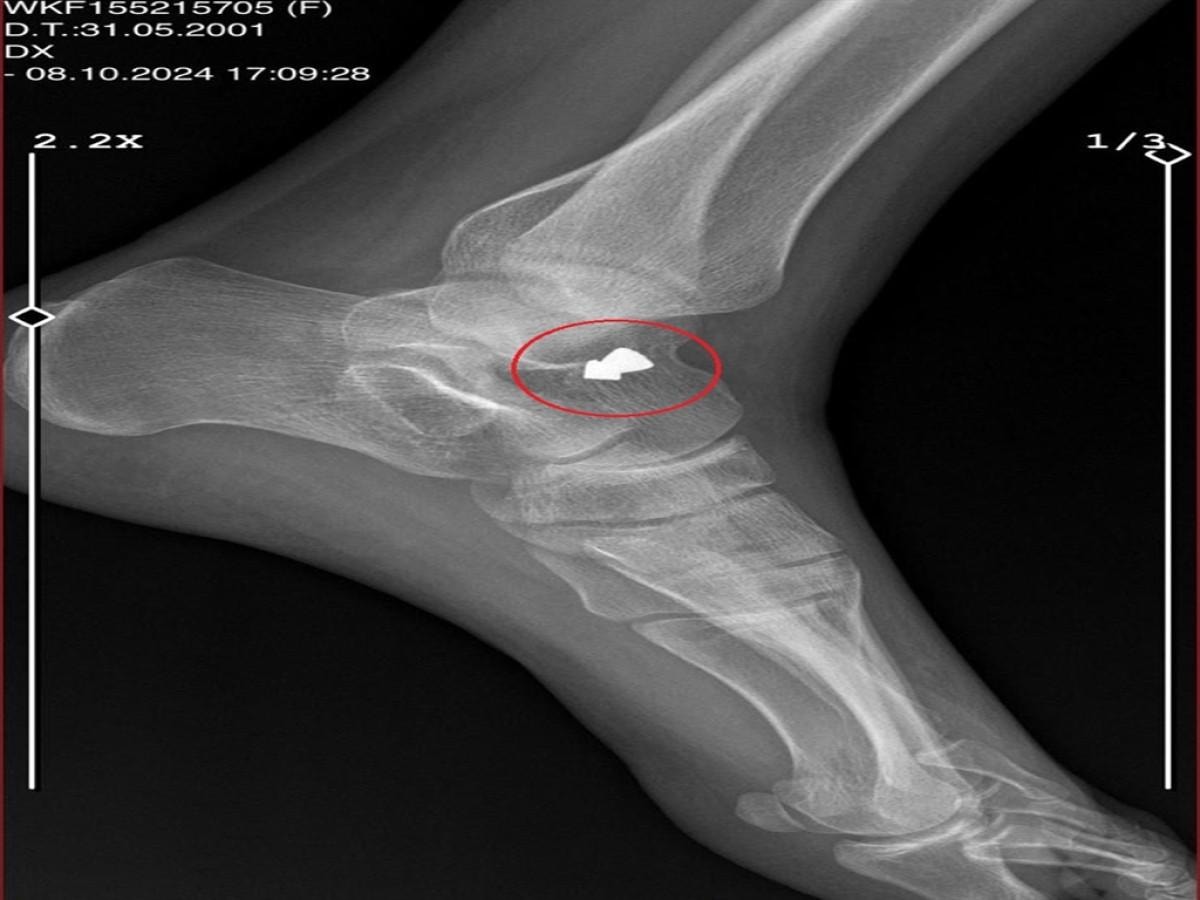

Ayak kemiğim çatlamış, alçıya bu yüzden aldılar. Eve geldiğimde e-Nabız uygulamasından röntgenime baktığımda, saçmanın ayağımın içinde kaldığını gördüm; ama beni bir daha hastaneye götürmedi" diye konuştu.

Yalova'ya döndükten sonra, 19 Ekim'de sol kemiğine isabet eden saçmanın ameliyat ile çıkarıldığını söyleyen Ayşe Ç., "Evden kaçabilmem için bir imkan yoktu. A.K., en son gün, evden gitmeden önce beni darbetti. Saçlarımdan tutarak, yerde ayakkabılarıyla tekmeledi. Sonra evden gitti.

Yolda yürürken bile, bakkala çıktığımda bile korkarak çıkıyorum. Biri yanımdan geçtiğinde korkuyorum. 1 ay ayağımda saçmayla gezdim. Ailemin yanına geldiğimde korkudan söyleyemedim.

Arkadaşıma konuyu anlattığımda, o beni hastaneye götürdü. Daha yeni ameliyat oldum. Saçmayı çıkarttılar, şu an dikişli ayağım. Bu insan, bende kalıcı bir hasar bıraktı" diye konuştu.